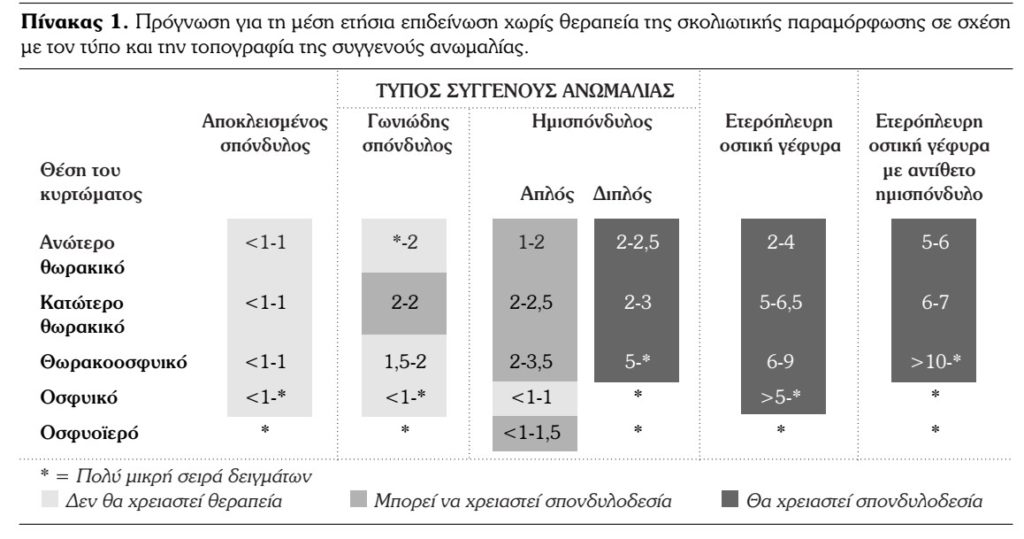

Μια έξοχη μελέτη για τη φυσική ιστορία και πρόγνωση της συγγενούς σκολίωσης είναι αυτή των McMaster και Otsuka, οι οποίοι συγκέντρωσαν στοιχεία από 251 ασθενείς, τα οποία απεικονίζονται στον πίνακα 1.

Στον πίνακα αυτό παρατηρούμε την πρόγνωση για τη μέση ετήσια επιδείνωση χωρίς θεραπεία της σκολιωτικής παραμόρφωσης σε σχέση με τον τύπο και την τοπογραφία της συγγενούς ανωμαλίας. Η αριστερή στήλη αναφέρεται σε ασθενείς στους οποίους η σκολίωση διαγνώσθηκε σε ηλικία <10 ετών. ενώ η δεξιά στήλη σε ασθενείς στους οποίους η σκολίωση διαγνώσθηκε σε ηλικία >10 ετών. Η ετήσια επιδείνωση υπολογίστηκε σε μοίρες.